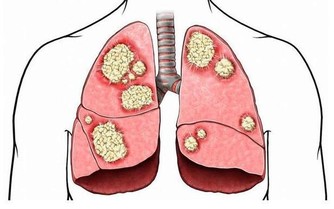

三酸甘油酯升高是心臟疾病的主要風險因素之一,包括心肌梗死、中風和動脈硬化。

主要是生活方式不良,造成代謝紊亂的病理狀態,增加患上心臟疾病、脂肪肝和嚴重癌症的風險。